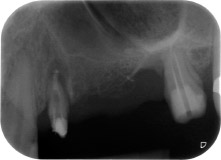

apical periodontal lesion at tooth 24

Fig. 1: 58-year-old patient. Preoperative radiograph showing an apical periodontal lesion at tooth 24 and horizontal loss of alveolar bone in the second quadrant.

A 58-year-old female patient complained of pain and increased mobility of her bridge abutment tooth 24. Periodontal inflammation was present with pocket depths of 7 mm mesiobuccally and more than 12 mm distally, as well as third-degree furcation involvement. Moreover, the radiograph revealed an extensive periodontal lesion around the apical region of the (alio loco) endodontically pretreated tooth 24 (Fig. 1).